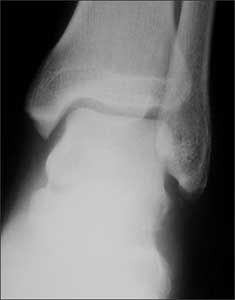

Right ankle pain after a basketball injury: The frontal view of the ankle reveals soft tissue swelling that is predominantly lateral (A, yellow arrow). A small ossific fragment is evident distal to the lateral malleolus (A, white arrow); close inspection shows this to be well-corticated. The remainder of the osseous structures are intact. The lateral view reveals a joint effusion in the talotibial joint (B, arrow); no fractures are visible. In the oblique view (C), the osseous structures appear intact.

The well-corticated ossific fragment is consistent with an old injury, but it is in the region that is now extremely tender. The joint effusion indicates that the current injury is severe. However, this is a nonspecific finding; joint effusions are seen with fractures and ligament and tendon injuries.